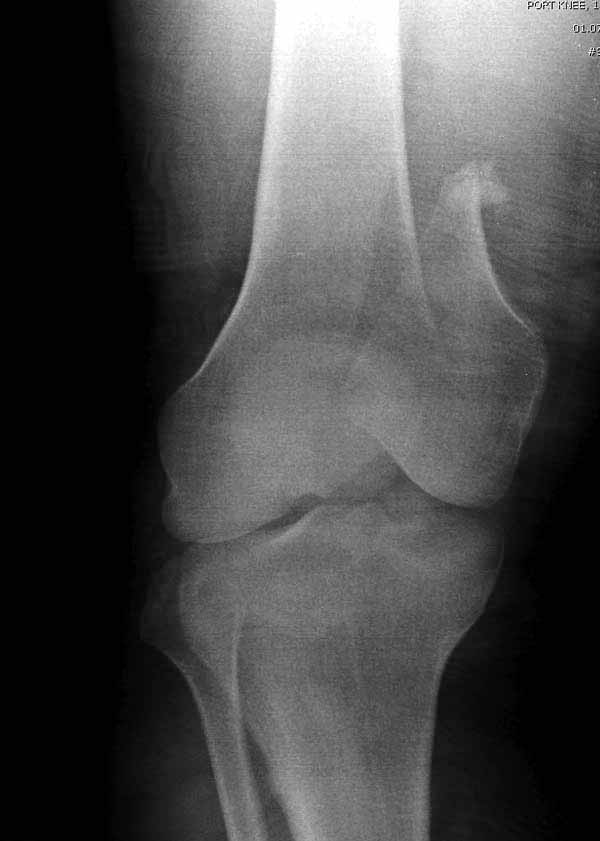

Представленный снимок не дает полную информацию. Там вроде простой перелом, но на самом деле, кроме смещенного (латерального, возможно медиального?) мыщелка на второй проекции имеется медиальный короткий дистальный фрагмент в флексии. Надо было сделать прямой снимок с захватом малоберцовой, который ориентировал бы стороны. Без КТ обычный снимок в дистракции поможет разобраться в топографии фрагментов.

Во время фиксации надо соблюдать осторожность, особенно с коротким фрагментом на другой стороне. Обычно на прямой проекции трудно заметить флексионную деформацию мыщелка и упускается адекватная фиксация. Без пластины винты не смогут удержать, и мыщелок на второй стороне может сместиться. Для фиксации надо развернуть мыщелок и удержать винтами. Качество межмыщелковой репозиции надо проконтролировать артротомией. Из всех доступов только передне-латеральный доступ (Swashbuckler) даст обзор для ревизии качества фиксации, который в будущем может быть использован для артропластики.

Кстати, из вашего снимка, если отмечены вашим рентгенологом правильно, тогда получается снимок левого колена, и, соответственно, длинный переходящий в диафиз мыщелковый фрагмент находится медиально. Если так, тогда меняется сценарий фиксации!!!

Сразу не обратил ваше внимание именно на это, что сломаны оба мыщелка, и больший является именно медиальным мыщелком, а пластины ставятся по латеральной стороне, соответственно, в этом медиальном мыщелке от пластины останутся только концы винтов, которые не обеспечат достаточной фиксации мыщелка.

И не обратите, коллега, пока не сделаете четкие анфасные снимки (лучше с дистракцией) где будет четко визуализироваться малоберцовая кость. Думается, что и КТ здесь будет уместно, дабы не пропустить возможное флексионное повреждение (перелом Hoffa).